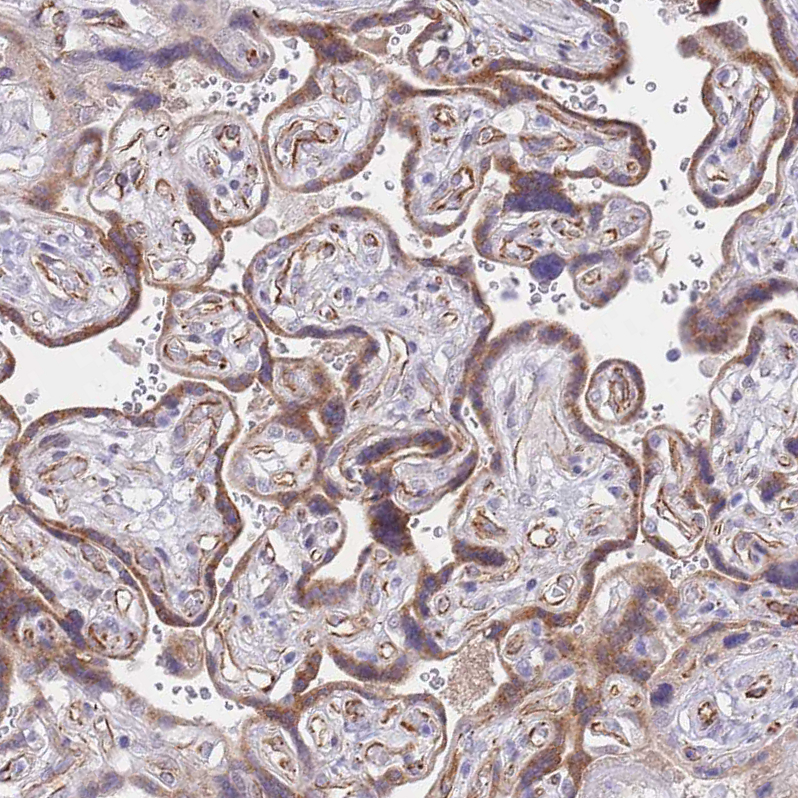

Immunohistochemical staining of human placenta shows strong cytoplasmic positivity in trophoblastic cells.